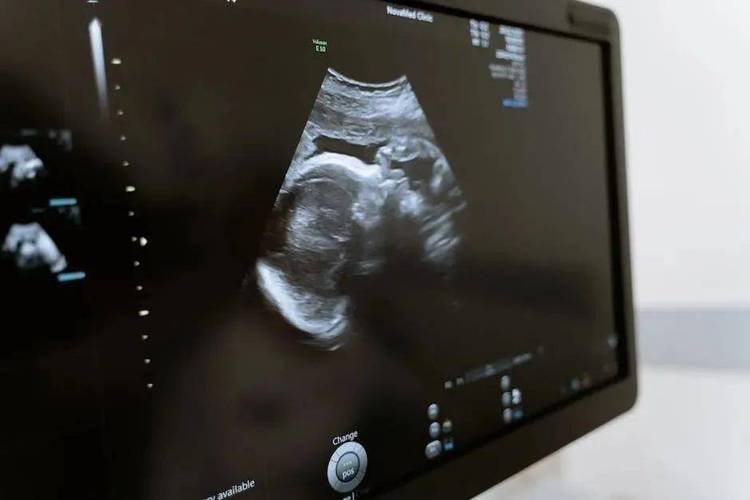

不同器官的b超检查有其重点观察内容,心脏超声需测量心腔大小、室壁厚度、瓣膜活动及血流情况,评估心脏功能;产科超声中,早孕重点观察孕囊、胎芽、胎心,中晚孕则需系统筛查胎儿结构(如头围、腹围、股骨长度,以及唇裂、心脏畸形等);甲状腺检查则关注结节的大小、形态、边界、内部回声及钙化情况,TI-RADS分级是评估甲状腺结节良恶性的常用标准,b超还可引导穿刺活检、囊肿抽液硬化等介入操作,实时显示针尖位置,提高操作安全性。